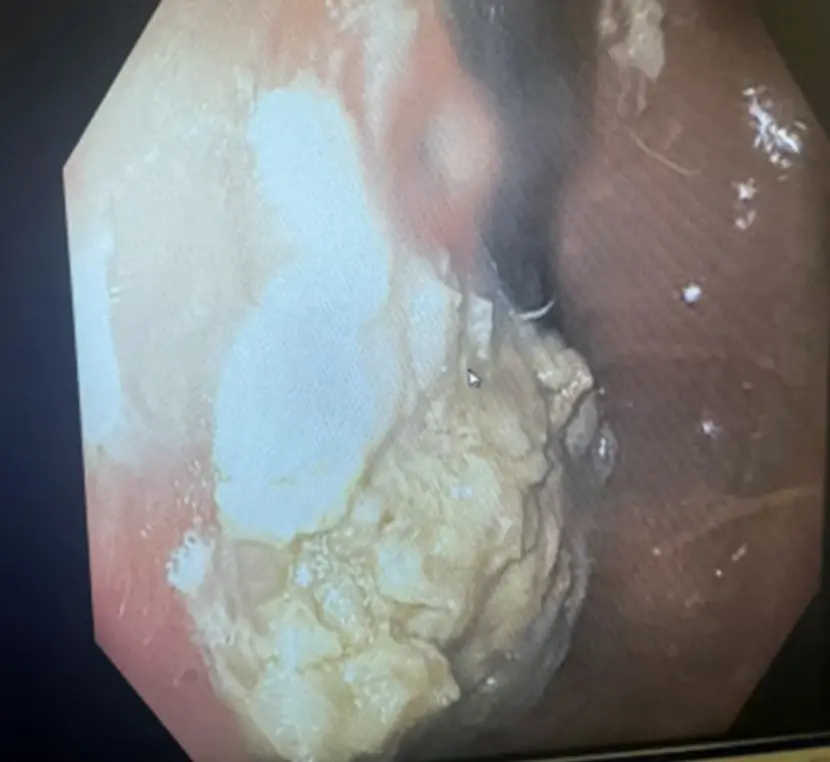

Οι γιατροί αφαίρεσαν την τσίχλα με άκαμπτη οισοφαγοσκόπηση, με τη βοήθεια ενός μεταλλικού σωλήνα και χρησιμοποιώντας λαβίδες για να πιάσουν τη μάζα.

Ο μικρός ασθενής είχε πονόλαιμο λόγω των πολλαπλών «περασμάτων» που έγιναν για την εξαγωγή της κολλώδους μάζας, αλλά τελικά πήρε εξιτήριο χωρίς η όλη περιπέτεια να έχει μακροχρόνιες επιπτώσεις στην υγεία του, σύμφωνα με τη μελέτη.